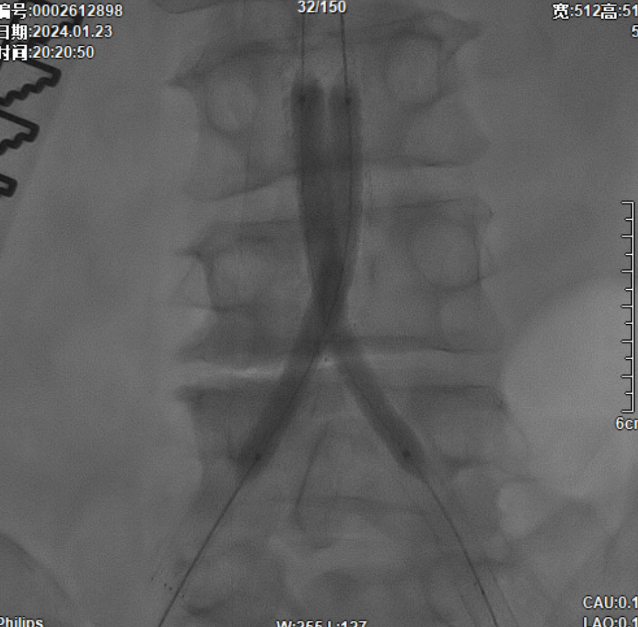

该图解释为何远端距离双侧髂总动脉分叉至少1.5cm,以避免后扩张时大球囊对髂动脉造成损伤。

CERAB技术的关键点一:经双侧股总动脉植入2枚VBX球囊扩张式覆膜支架(8L×79mm),与腹主动脉覆膜支架腔内平行放置,且两枚支架端平齐对接。

CERAB技术关键点二:先用14mm×40mm球囊分别扩张双侧髂肢的腹主动脉段。

再用8mm球囊对双侧髂支腹主动脉段行对吻扩张,以确保双侧髂支与腹主动脉覆膜支架腔内获得良好的贴壁形态,最大程度减少空腔,降低远期再狭窄发生率。